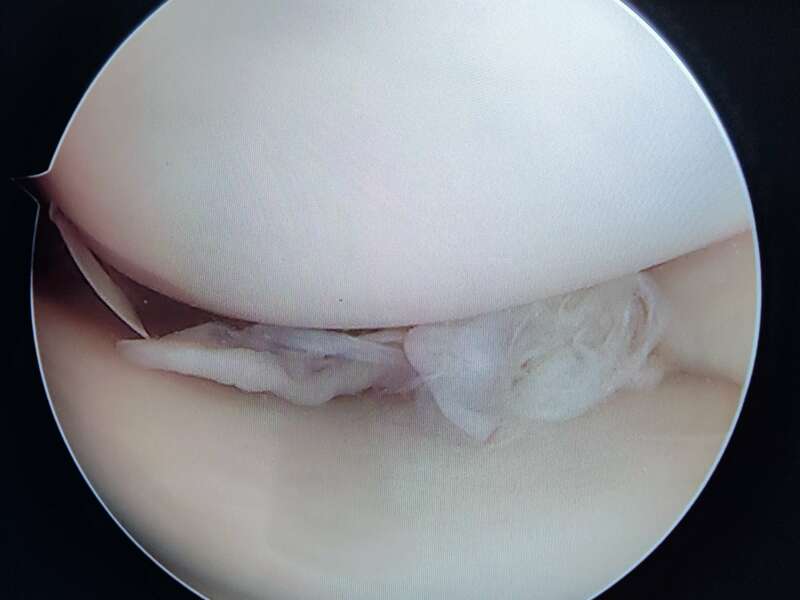

L’anse de seau méniscale est une fissure verticale qui s’étend de la corne postérieure à la corne antérieure. Cette anse est le plus souvent luxée dans l’échancrure inter-condylienne et provoque des blocages en extension.

Les douleurs sont généralement brutales et intenses avec un gonflement du genou. Le blocage en extension de votre genou correspond à une luxation méniscale dans l’échancrure inter-condylienne (espace situé entre les ligaments croisés et le condyle fémoral). On parle alors de fissure en anse de seau.

La plupart du temps, les lésions méniscales traumatiques sont traitées chirurgicalement. Deux gestes sont possibles : la réparation méniscale et la méniscectomie. Ces deux interventions sont réalisées au cours d’une arthroscopie et ont des indications spécifiques à chacune.